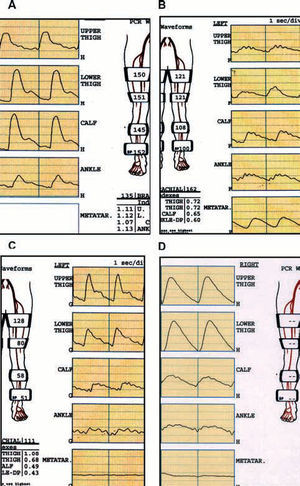

Recording the pulse wave volumes along the limb by plethysmography is particularly useful in patients in whom arterial calcification prevents a reliable recording of systolic pressures. Transmetatarsal or digital recording provides important information about the state of the vascularization in this zone, which is difficult to obtain with other techniques (Figure 1).

Figure 1. Study of segmental pressures and wave volume according to the affected sector. A: normal study: pulse wave volumes (PWV) with dicrotic wave. Segmental indices >1 at all sites. B: iliac occlusion: flattening of the PWV and indices <1 from the proximal thigh. C: femoropopliteal occlusion: normal PWV and indices in proximal thigh. Distal flattening of PWV with index <1 in ankle. D: intense calcification: the vessels do not collapse despite the very high sleeve pressures (falsely high ankle-arm index). Very pathologic PWV, transmetatarsal planes.